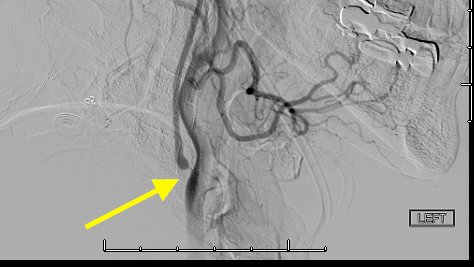

Criteria 2: Delayed contrast filling of the ipsilateral internal carotid artery (ICA) compared to external carotid artery (ECA).

In this carotid injection, stagnant contrast remains within the patient's ICA even after clearing the ECA circulation.